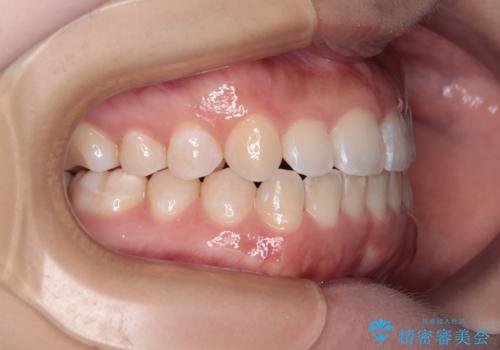

前歯のクロスバイトを改善 インビザライン・モデレートによる矯正治療

- 上下前歯のクロスバイトと叢生を気にして来院された患者様です。

インビザラインでの治療を希望されていて、デコボコの程度が中等度であり、安価なパッケージにて対応可能と判断されたため、インビザライン・モデレートを用いて矯正治療を行うこととしました。

モデレートパッケージは、アライナー数や期限に制約がある一方、安価に治療を行うことができるパッケージです。

アライナー数が制約数内に収まるかどうかはシミュレーションを作成するまで不明なため、すべての方に適用されるものではありません。